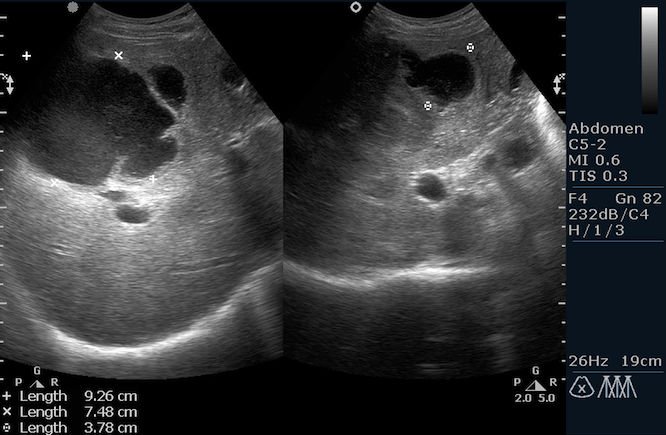

УЗИ поясничной зоны

Положение пациента при данной процедуре – лежа, причем на спине. Датчик врач перемещает по брюшной стенке. Эта особенность проведения процедуры связана также с закрытостью поясничной зоны сзади непроницаемыми костными пластинками. При этом виде УЗИ положено пройти специальную подготовку, включающую очистку кишечного содержимого, поскольку в исследовании задействованы верхние кишечные отделы.

УЗИ поясничного отдела

Проведение процедуры позволяет стать обладателем следующей информации:

- состояние дисков;

- их изношенность;

- присутствие протрузий;

- имеющиеся грыжи;

- состояние желтой связки и ее отек;

- аномальное развитие позвоночных структур, формирующих столб;

- качество и количество спинномозговой жидкости.